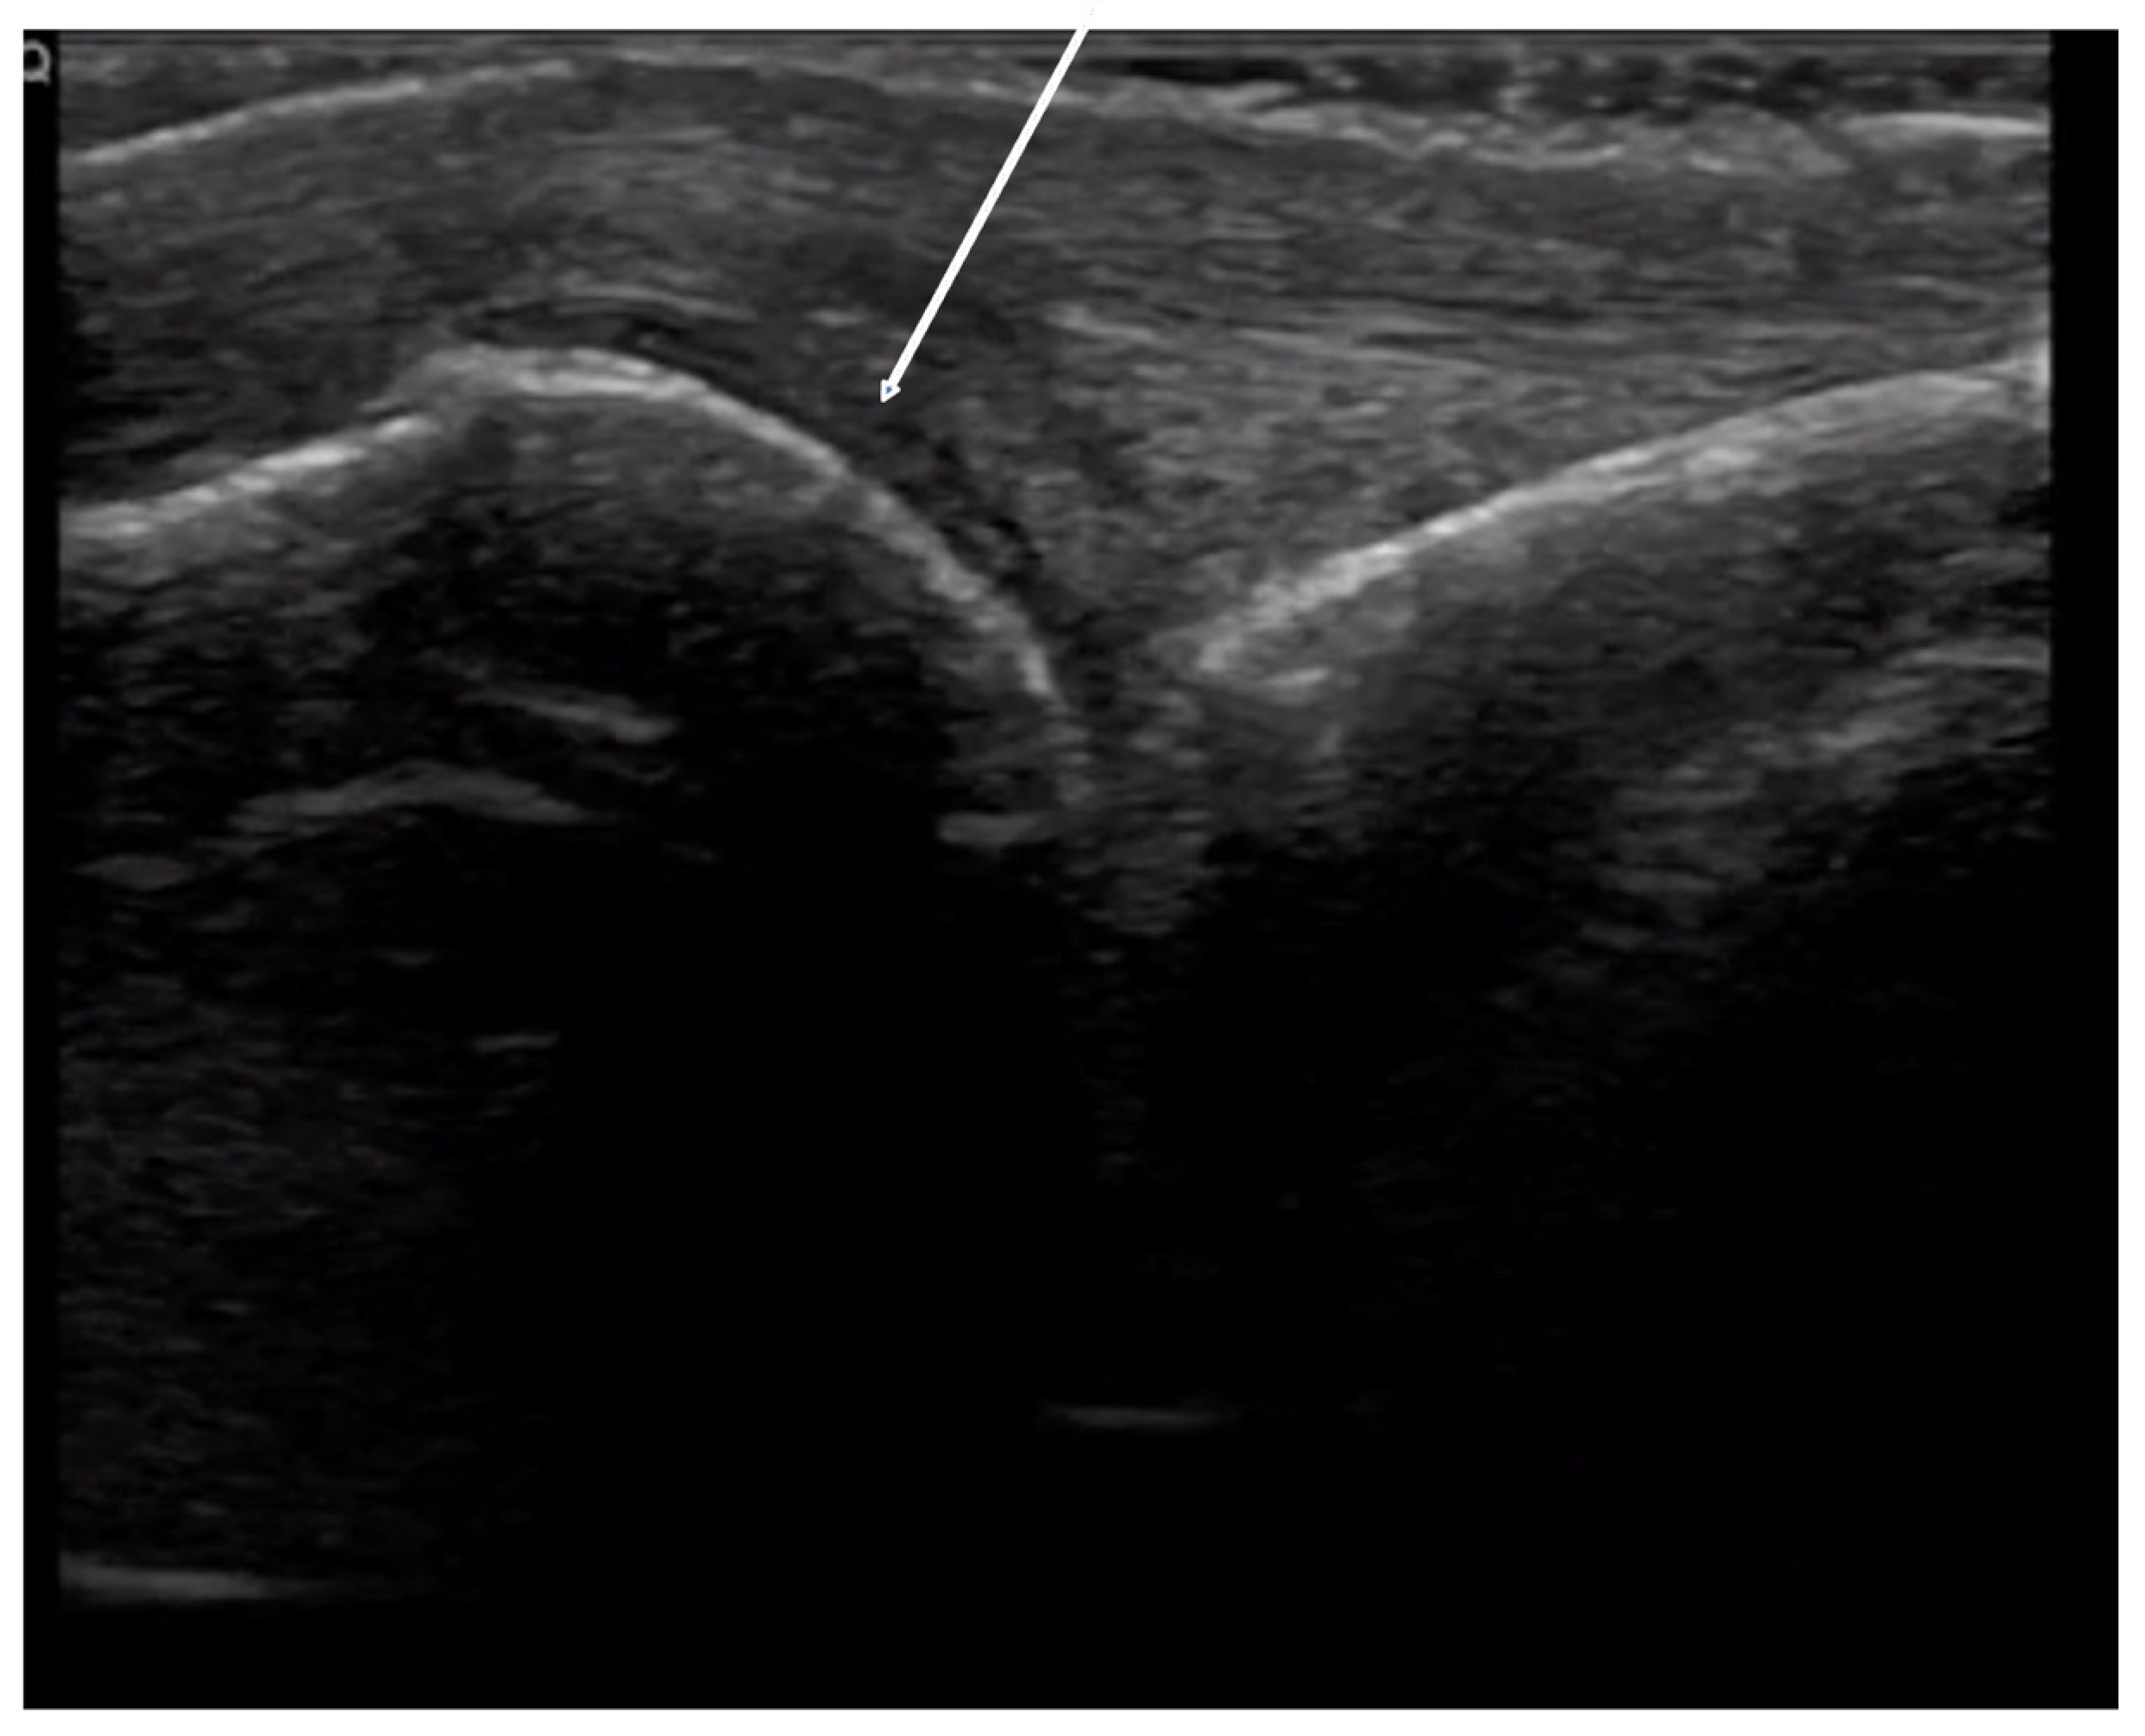

4.2.3. Ulnar Aspect